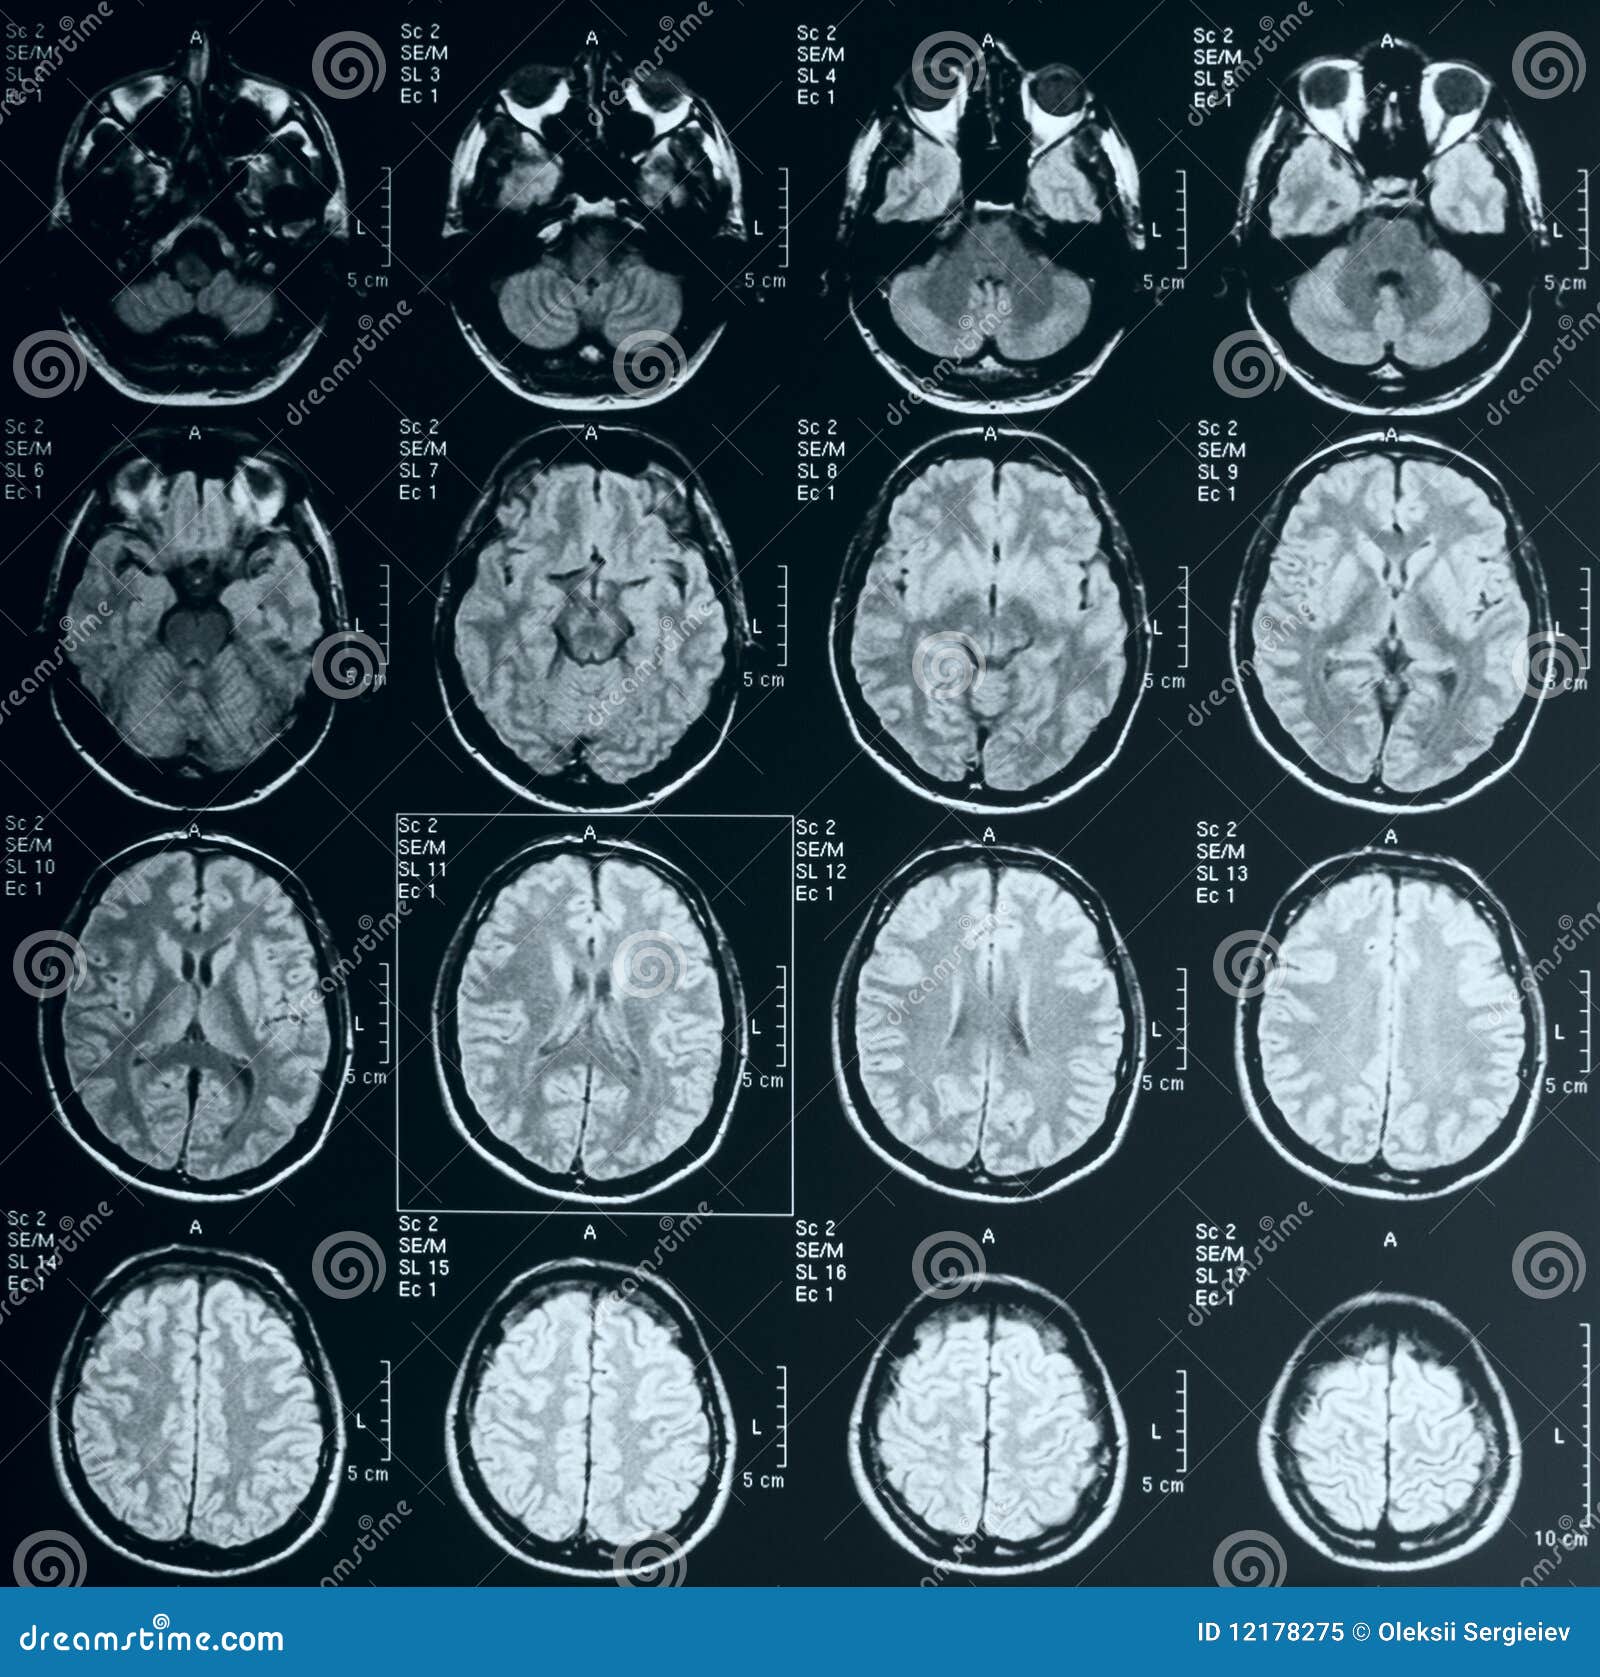

Подробное руководство по МРТ мозга спереди

В этом разделе вы найдете примеры снимков МРТ мозга в передней проекции, полезные советы для подготовки к обследованию, а также узнаете, что можно увидеть на таких изображениях.

МРТ головного мозга, что позволяет выявить?

Что показывает МРТ головного мозга

Что скрывает МРТ головного мозга